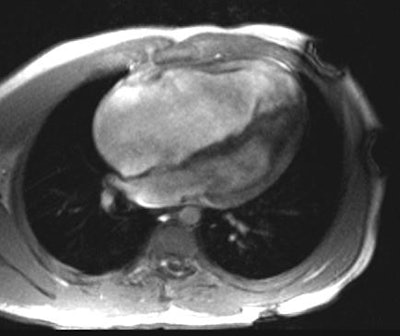

Ebstein's Anomaly:

The axial cine-GRE MR image on the left was obtained at end-systole and the right image at end-diastole. There is massive right atrial enlargement and the tricuspid valve leaflets are extremely long, extending down nearly to the right ventricular apex. There is marked "atrialization" of the right ventricle; and there is almost no coaptation of the valve leaflets during systole.